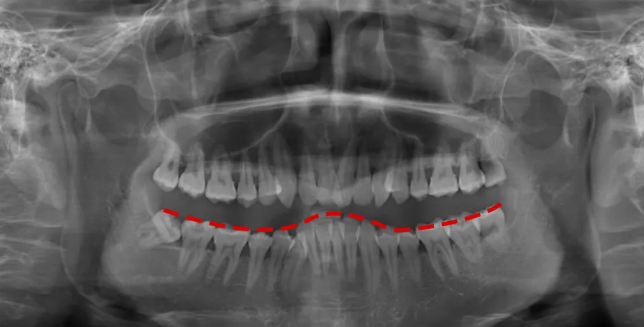

🔎牙周情况

△正常情况下,牙槽骨高度位于牙根与牙冠的交界处下方一点(白色线标注位置)。